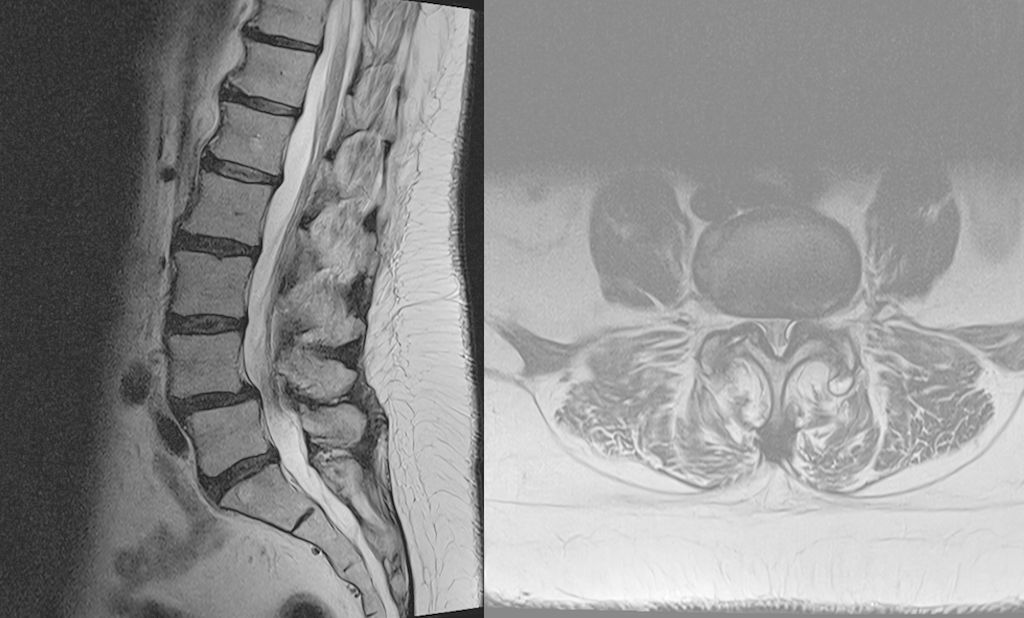

Fallbeispiel 2

TLIF über Mittellinienzugang mit Schrauben in „cortical bone trajectory“. Bei der 63-jährigen Patientin bestand eine degenerative Spondylolisthese Meyerding Grad I mit Facettengelenkszysten und Wirbelkanalstenose (Abb. 8). Klinisch bestanden Lumboischialgien mit Ausstrahlung dem Dermatom L5 bds. entsprechend. Es wurde ein Mittellinienzugang durchgeführt und zuerst wurden navigierte Schrauben in „cortical bone trajectory“ platziert (Abb. 9). Anschließend erfolgten eine Facettektomie L4/5 links und eine Dekompression des Wirbelkanals. Abbildung 10 zeigt, dass der Hautschnitt aufgrund der mittelliniennahen Schraubenköpfe klein gehalten werden kann. Klinisch wurden die lumbalen Schmerzen wie ausstrahlende Beschwerden 1 Jahr postoperativ annähernd vollständig behoben, die korrespondierende Röntgenkontrolle ist in Abbildung 11 dargestellt.